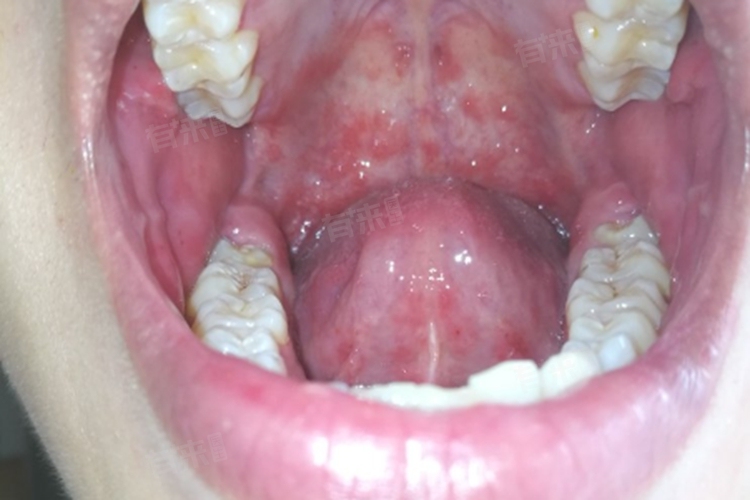

1、黏膜红肿与疼痛:口腔炎症初期,患者常会感到口腔黏膜红肿、充血,并伴有不同程度的疼痛感,这是由于细菌、病毒或真菌感染侵入口腔黏膜后,引发的炎症反应所致,红肿与疼痛可波及颊黏膜、舌、齿龈、上腭等多处口腔黏膜。

3、疱疹:在疱疹性口腔炎中,患者口腔黏膜上会出现簇集性小水疱,这些水疱容易破裂形成糜烂面,并伴有疼痛感。疱疹可发生于口腔的任何部位,但以舌、颊黏膜、唇等部位多见,疱疹性口腔炎多由单纯疱疹病毒引起,具有传染性。